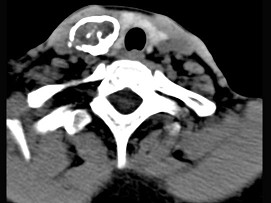

5.男性,40歲,頸部出現(xiàn)無(wú)痛性囊性包塊2年余,CT掃描如圖所示,最可能診斷為  (    )

正確答案:A